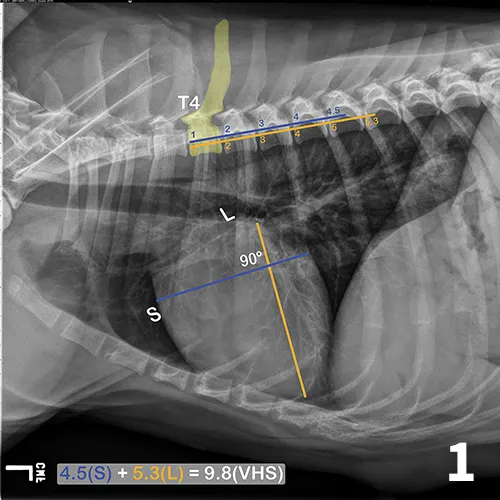

A lateral thoracic radiograph of a normal dog with measurements added to evaluate heart size compared to the thoracic vertebrae.

FIGURE 1

Illustration of VHS calculation in a normal dog. On a lateral radiograph, a line is drawn from the carina to the most ventral aspect of the heart. This line is the “L” or long axis line. A line is drawn perpendicular to the long axis at the widest portion of the heart, extending to the cranial and caudal borders. This is the short axis or “S” line. These lines are transposed using calipers extending along the spine from the cranial aspect of T4. The number of vertebrae traversed (rounded up to the nearest tenth) are added together for the VHS.